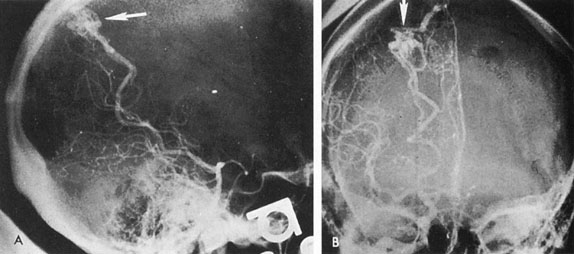

Of particular interest are those AVMs that involve the occipital lobe (Fig. 9). The clinical differentiation of migraine from a cerebral AVM was previously regarded as difficult because the clinical features of occipital lobe AVMs include visual phenomena or headaches. However, in most cases the clinical distinction is possible. In 26 cases with occipital AVM, two distinct syndromes were defined in 18 patients: occipital epilepsy and occipital apoplexy.73 Focal seizures with occipital malformations consist of elementary visual sensations similar to the phenomena evoked by direct cortical stimulations. When seizure activity occurs in the striate cortex (area 17), the patient usually reports sensations of moving lights in the right or left homonymous fields. The sensations are poorly formed, episodic, usually brief, sometimes colored, and unassociated with the angular, scintillating figures so characteristic of migrainous cortical phenomena. Epileptic discharges from areas 18 and 19 cause photopsias that are unlikely to remain stationary and to flicker rapidly. The epileptic photopsias usually last only seconds; occasionally they last for a few minutes before the onset of a generalized seizure. In other instances only the brief visual episodes occur without spreading to produce a generalized seizure. Momentary dimming or blindness in one or both homonymous fields may be experienced with seizure activity in the occipital areas.

Fig. 9. Carotid arteriogram of an occipital lobe arteriovenous malformation (AVM). Lateral (A) and frontal (B) projections demonstrating a small occipital AVM (arrow). The patient was a 23-year-old woman who presented with severe apoplectic unilateral headache, total left homonymous hemianopia, and mild nuchal rigidity. Despite xanthochromic cerebrospinal fluid, she was initially diagnosed elsewhere as having migraine. An AVM was successfully resected, and a small occipital lobe hematoma was removed.

Occipital apoplexy results from hemorrhage and hematoma formation within the occipital lobe and is characterized by sudden severe headache and homonymous visual field loss. Homonymous hemianopia is the most important sign produced by vascular malformations of the occipital lobe. Compression and necrosis of visual pathways by an intracerebral hematoma are the principal mechanisms. Usually the hematoma is large and tends to split or dissect longitudinally through the white matter of the occipital lobe. The effects of compression may be reversed by prompt, surgical evacuation of the hematoma.73 With hemorrhage into one occipital lobe, hemianopia in the visual field of the contralateral normal occipital lobe may develop, producing total blindness that can last for several days. The rapidly expanding hematoma may shift the damaged hemisphere anteriorly, or across the midline, with downward herniation of the uncus through the tentorial incisura. This shift compresses the posterior cerebral arteries and accounts for bilateral occipital lobe dysfunction. Arrest of function in the undamaged occipital lobe may be due to an interhemispheral inhibitory phenomenon termed diaschisis. Visual field defects with occipital AVMs are regularly due to hemorrhage and hematoma formation. Congenital arteriovenous malformations can occupy the entire occipital pole (the macular projection area) for decades without producing visual field defects.

Although migraine is often cited as a symptom of AVM, it is extremely rare that classic migraine is mimicked by occipital AVM. None of the patients in the series by Troost et al73 described the 15- to 20-minute episodes that characterize the visual aura of classic migraine. The headaches of AVM differ from migraine in that they are constantly localized to the same side of the head, and intermittent visual phenomena, if present, can persist throughout the headache or even after, whereas in migraine the visual phenomena usually precede the headache. Bruyn74 has reviewed the clinical features of 57 reported and 7 personal cases of AVM, concluding that the migraine of AVM is late onset, nonfamilial, and brief. Rarely, the complete clinical symptomatology of classic migraine can be mimicked by an occipital lobe AVM (see Chapter 16).75 In addition to hemianopia, other visual disturbances can occur after hemorrhage into the occipital lobe, including alexia without agraphia (see Chapter 7).